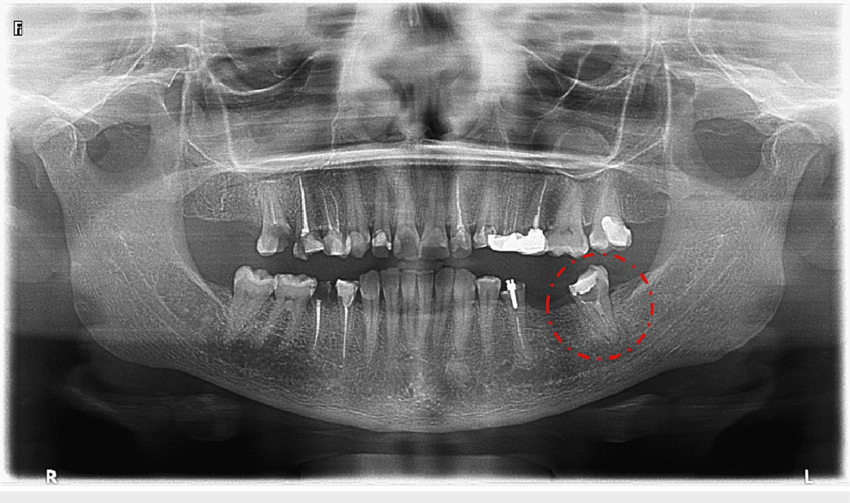

Orthopantomogram (OPG)

An Orthopantomogram (OPG) is a panoramic dental X-ray that provides a comprehensive view of the upper and lower jaws, teeth, and surrounding structures in a single image. This non-invasive imaging technique is essential for diagnosing dental conditions such as impacted teeth, cavities, bone loss, and jaw abnormalities.